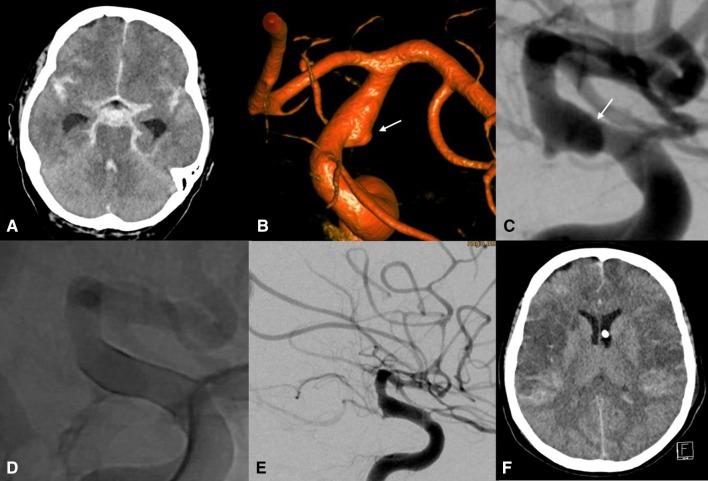

Eight patients were identified. The mean interval between aSAH and FD was 6 days. Of the eight ruptured aneurysms, one was blister-like, one saccular, one mycotic, and the remaining five were dissecting aneurysms. Intraprocedural transient thrombus formation was observed in four patients (50%). Stent thrombosis was observed in one patient (12.5%) on day 3 with spontaneous recanalization after being switched onto DAPT. None of the aneurysms rebled after treatment. Two patients died due to cerebral vasospasm. Complete aneurysm occlusion had been achieved in all but one patient at angiographic follow-up (average 6 months).

共确定了 8 例患者。aSAH 与 FD 的平均间隔为 6 天。8 个破裂的动脉瘤中,1 个为泡状,1 个为囊状,1 个为真菌性,其余 5 个为夹层动脉瘤。4 例(50%)患者术中观察到短暂血栓形成。1 例患者(12.5%)在第 3 天出现支架内血栓形成,在改用 DAPT 后自发再通。治疗后无动脉瘤再出血。2 例患者因脑血管痉挛死亡。血管造影随访时,除 1 例患者外,所有患者的动脉瘤均完全闭塞(平均随访 6 个月)。